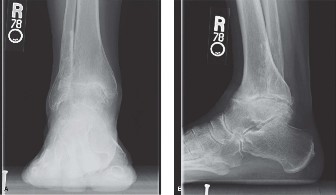

A 48-year-old female presents to your office with worsening right ankle pain. Twenty years ago she sustained …